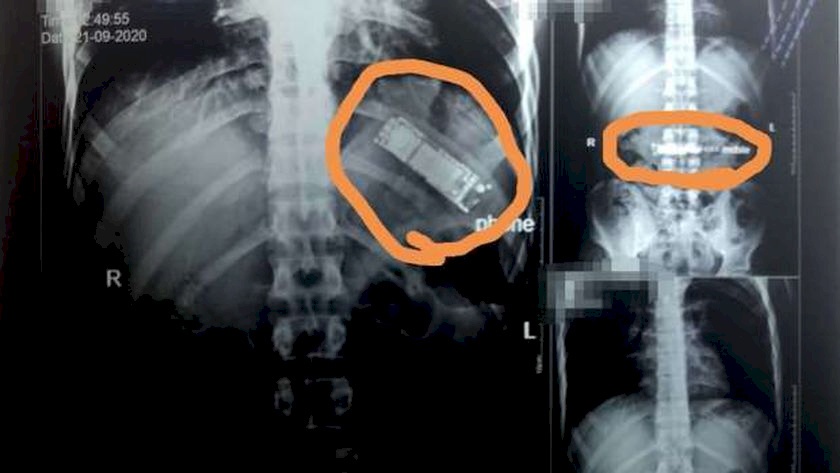

صدى نيوز: في واقعة غريبة، عثر أطباء مصريون على هاتف محمول في معدة مواطن قام بابتلاعه منذ 7 أشهر.

وأدخل المريض، وهو من مدينة كفر شكر بالقليوبية، إلى مستشفيات بنها الجامعية، حيث أجريت له فحوصات بأشعة تلفزيونية على الصدر والبطن، كشفت عن وجود هاتف محمول في معدته، بحسب الدكتور محمد الجزار، استشاري أورام الصدر وأستاذ جراحة القلب والصدر والمناظير بكلية الطب في جامعة بنها.

وأوضح الجزار، أن المريض أكد أنه ابتلع الجهاز منذ 7 أشهر على سبيل المداعبة مع أصدقائه دون أن يعلم أي فرد من أبناء أسرته، موضحاً أنه بسؤاله عن سكوته طوال هذه الفترة، أكد أنه كان يظن أن التليفون سيخرج بمجرد حدوث استرجاع بالمعدة مرة أخرى، إلا أن هذا لم يحدث حتى الآن.

وتابع الطبيب، أنه تم تحويل المريض لقسم الجراحة العامة بالمستشفى، ويتم إعداده حالياً ووضعه بقائمة الجراحات تمهيداً لإجراء الجراحة سريعاً والتعرف على نوع التليفون وكيفية ابتلاعه.